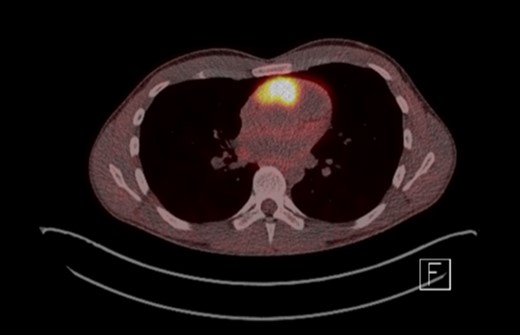

A 26-year-old male, with a family history of PGL4, presented with an 18-month history of paroxysmal headaches, a one-month history of frequent diaphoresis, anxiety attacks and unintentional weight loss of one stone in two months. His father and brother had previously been diagnosed with PGL4 and had undergone surgical resections for abdominal and pelvic paragangliomas. He underwent biochemical and genetic work-up confirming significantly elevated plasma normetanephrines and 3-methoxytyramines, with normal plasma metadrenaline levels. Full body CT, MR (Fig. 1) and 18F-fluorodeoxyglucose positron emission tomography (FDG-PET) CT imaging (Fig. 2) revealed a left para-aortic mass in the mid abdomen and a mediastinal lesion located between the root of aorta and origin of the main pulmonary artery, encroaching the right ventricle.

FDG-PET scan showing 3.8 × 2.6 × 5.5 cm highly FDS avid lesion between root of aorta and origin of pulmonary artery.